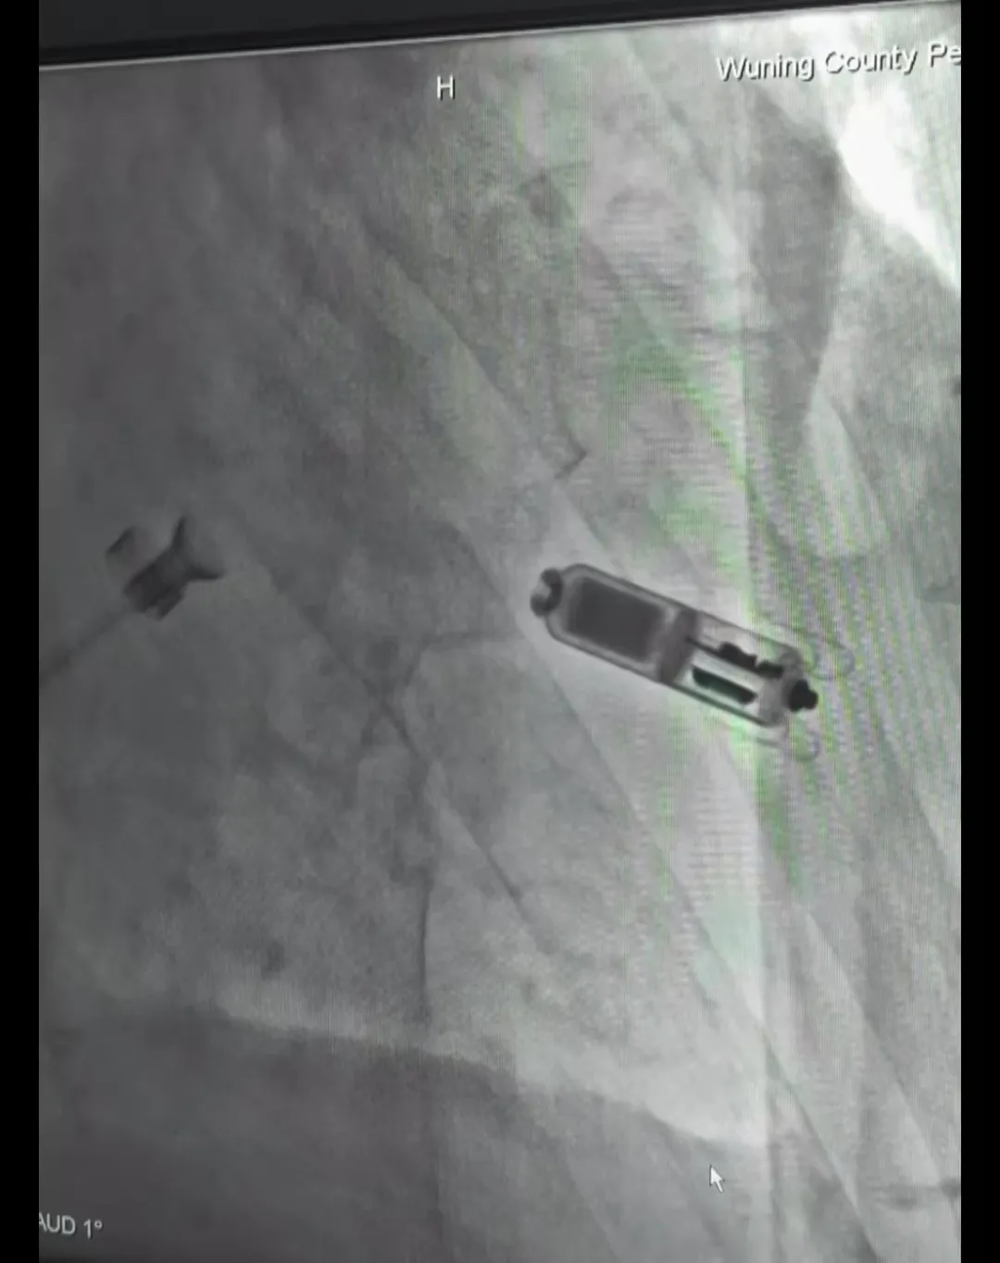

2024年7月5日,醫院心血內科團隊成功完成了(le)贛西北縣級醫院第一例(lì)無導線起搏(bó)器Micra植入手術(shù)。此次手術標(biāo)誌著武寧縣總醫院(yuàn)人民醫院院區心血管內科在心髒起(qǐ)搏(bó)領域邁上了新的台階,實(shí)現了新的診療突破。

在江西省人民醫院心血管病醫院盛(shèng)國太副院長指導下(xià),葛運豐、王強主(zhǔ)任等心血(xuè)管內科介(jiè)入手術團(tuán)隊為患者進行局(jú)部麻醉(zuì)後,通過股靜(jìng)脈穿刺將起搏器通過導(dǎo)管順利植入心腔內部。整個過程不到(dào)1小時,患者在整個植入過程中保持清醒狀態,可隨時(shí)與醫生溝通。術後(hòu)患者症狀明顯改善,活動不(bú)受限製,精神狀(zhuàng)態良好,取得了非(fēi)常好的療效。